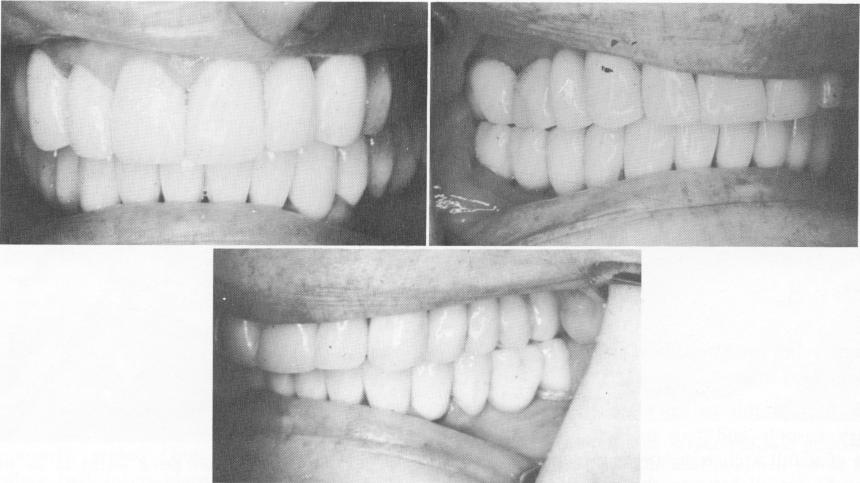

Fig. 11-65. Upper and lower restorations cemented in place.

Fig. 11-66. The anterior, left, and right lateral views of the completed case.

1 Upper and lower dental restorations cemented in place

2 Anterior,left,& right lateral views of upper & lower arch restorations